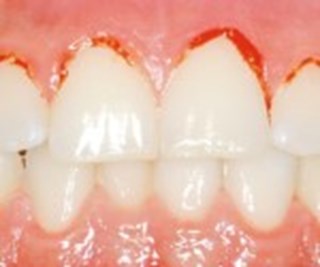

Petar man på ett inflammerat tandkött så blöder det.

Inflammerat tandkött